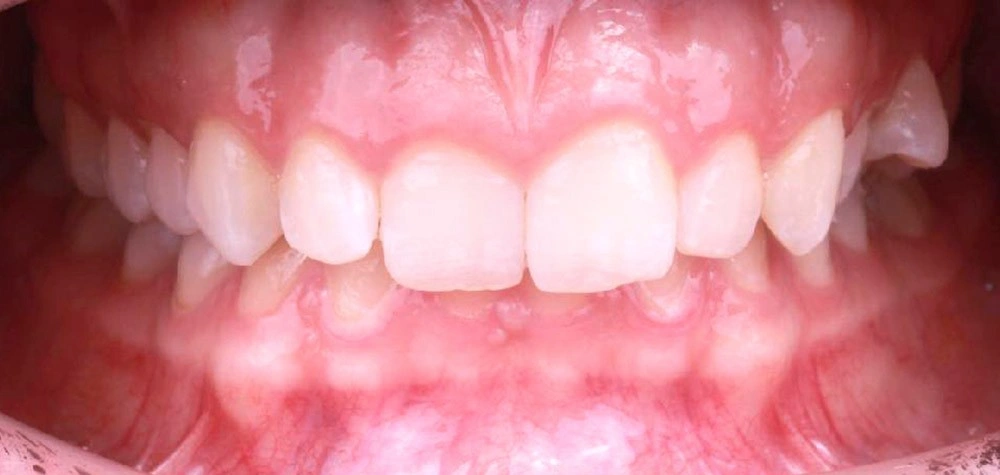

Глубокий прикус - Кейс 5

Эффективность устранения дефекта прикуса посредством элайнеров FlexiLigner.

Результаты лечения